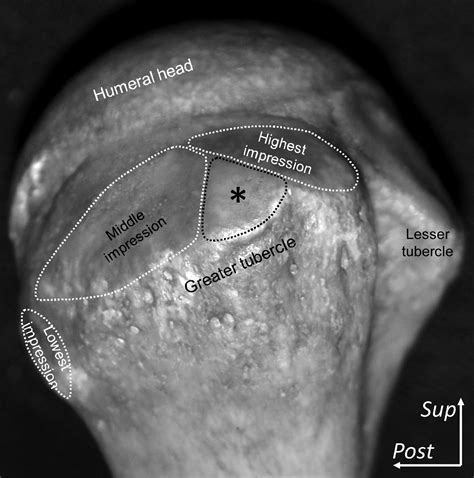

The greater tubercle of humerus is situated on the lateral aspect of the humeral head, adjacent to the articular surface. It is one of two key projections at the top of the humerus, the other being the lesser tubercle, which sits anteriorly. Separating these two structures is the bicipital groove, also known as the intertubercular sulcus, which houses the long head of the biceps brachii tendon.

The surface of the greater tubercle is distinctively roughened, providing an optimized surface area for the insertion of three of the four rotator cuff muscles. This anatomical positioning is not accidental; it provides the mechanical advantage necessary for the shoulder joint to execute movements like abduction and external rotation. The specific arrangement of these muscle attachments is described below:

• Supraspinatus: Attaches to the superior facet of the greater tubercle.

• Infraspinatus: Attaches to the middle facet.

• Teres Minor: Attaches to the inferior facet.